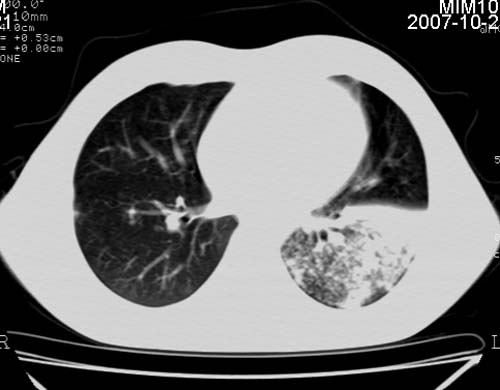

男,21岁,咳嗽、胸闷、乏力伴多汗二十余日、无明显发烧。患者一般情况好,为初三学生。

右肺上叶前段及左肺下叶多形性病变伴厚壁空洞,周边示树芽征.左肺下叶不张改变.

考虑;肺结核,不除外左肺下叶支气管内膜结核.

双肺继发性肺结核伴左侧空洞形成!不除外合并霉菌感染!(双肺多发病灶,左侧病灶形成空洞,并空洞内见壁结节。建议改变体位,观察空洞内结节情况,以便排除霉菌感染!)

左下肺实变能给出合理解释吗?